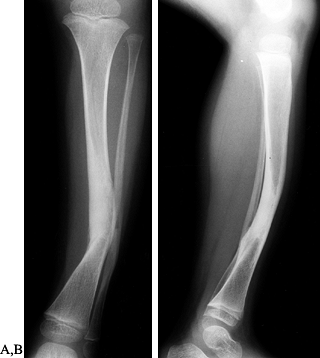

begins to improve by longitudinal growth through the proximal and distal physes (Fig. 169.15) (216). Unfortunately, there are no data indicating how much improvement can be anticipated. Salter and Best (244) found no improvement in 21 patients, and 13 later required proximal tibial varus osteotomies. Visser and Veldhuizen (281)

![]() |

Figure 169.15. A:

Standing AP radiograph of a 5-year-old boy after treatment for a greenstick fracture of the right proximal tibial metaphysis. At the time of cast removal, there was already 22° of genu valgum on the right but only 5° on the left. B: One year later, there was increased genu valgum deformity. |